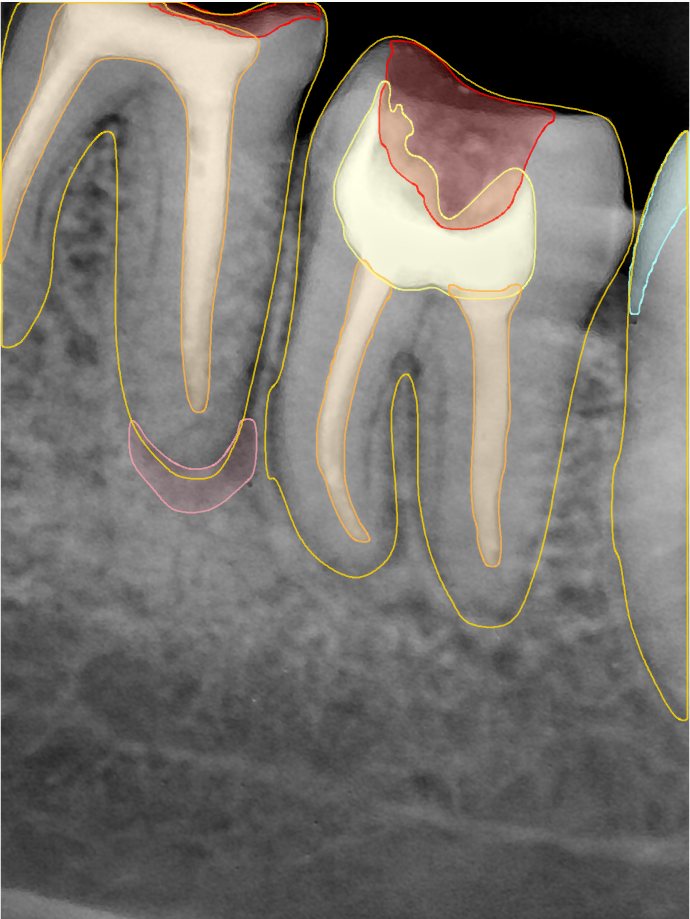

第二版算法问题测试

Updated: 2026-04-13(更新日期)

| 第一版 | 第二版 | 是否解决 | |

|---|---|---|---|

![]() | ![]() ![]() 边角识别有问题 龋齿识别不全 牙髓识别不全 | ![]() | 解决 |

![]() | ![]() 边角识别有问题 识别信息有误 自查(牙冠识别不全) | ![]() | 解决 |

![]() | ![]() ![]() 边角识别有误 大范围填充识别遗漏 | ![]() | 解决 |

![]() | ![]() 识别信息不全 | ![]() | 解决 |

![]() | ![]() ![]() 边角问题 牙胶识别不全 牙冠识别不全 | ![]() | 解决 |

![]() 换图片 | ![]() | ![]() 牙冠部分稍微白了一些就识别成小范围修补,部分判断异常 | 部分解决,修复类略敏感,牙冠部分稍微白了一些就识别成小范围修补,部分判断异常。 |

![]() | ![]() ![]() 牙冠识别不全 牙髓不全 根尖炎龋齿识别有误 | ![]() | 解决 |

![]() | ![]() | ![]() | 解决 |

![]() 换图片 | ![]() | ![]() | 解决 |

![]() | ![]() 牙冠识别有误 | ![]() | 解决 |

![]() 换图片 | ![]() ![]() 边角识别有误 | ![]() 修复类敏感 | 部分解决,图像过白,导致修复类判断异常。 |

![]() 换图片 | ![]() 牙冠识别不全 | ![]() 修复类敏感 | 部分解决,图像过白,导致修复类判断异常 |

结论:修复类出现了不鲁棒的情况,后续需要加入轮廓的扩充数据进行增强。